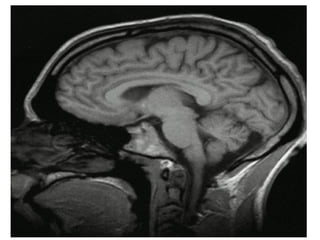

Encéfalo Cerebro,  cerebelo ,  tronco   Se aloja en la cavidad craneal Techo: Calota Suelo: Base del  cráneo  Porciones : Cerebro Hemisferios  cerebrals Diencéfalo  Mesencéfalo  Puente  Bulbo  raquídeo  Cerebelo